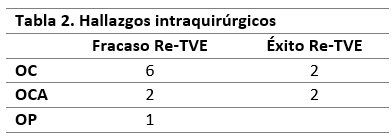

Como hallazgo intraquirúrgico, en 8 casos (62%) se constató el cierre completo de la ostomía, en 4 (30%) se observó el cierre de la ostomía por aracnoiditis, mientras que solo en 1 caso (7%) la ostomía permanecía permeable (Figura 2).

Tabla 2. Cuadro comparativo de los hallazgos intraquirúrgicos observados durante la Re-TVE en los casos de fracaso y éxito del procedimiento. OC: ostomía cerrada, OCA: ostomía cerrada con aracnoiditis, OP: ostomía permeable.

Durante la revisión endoscópica, los posibles hallazgos quirúrgicos en relación a la TVE son: 1) ostoma cerrado completamente, 2) ostoma cerrado por la presencia de aracnoiditis o 3) ostoma permeable.17,20,22,23 En el estudio multicéntrico publicado por Breimer et al. observaron una mayor tasa de éxito en aquellos pacientes que durante la Re-TVE la ostomía se encontró completamente cerrada. Mientras que aquellos pacientes en los que hallaron aracnoiditis en la cisterna presentaron una mayor tendencia a requerir un sistema de derivación dentro de los 6 meses.2 Siomin et al. presentó 20 pacientes, en todos los casos el ostoma se encontró completa o parcialmente cerrado, mientras que Koch y compañía en su serie de 12 casos, describieron 9 pacientes con ostoma totalmente cerrado y 3 en quienes presentaban una membrana aracnoidea.15,25 Al igual que lo expuesto en la bibliografía, de los 13 casos presentados en nuestro trabajo, 8 presentaron el cierre completo de la ostomía, 4 aracnoiditis y 1 solo caso de ostomía permeable.